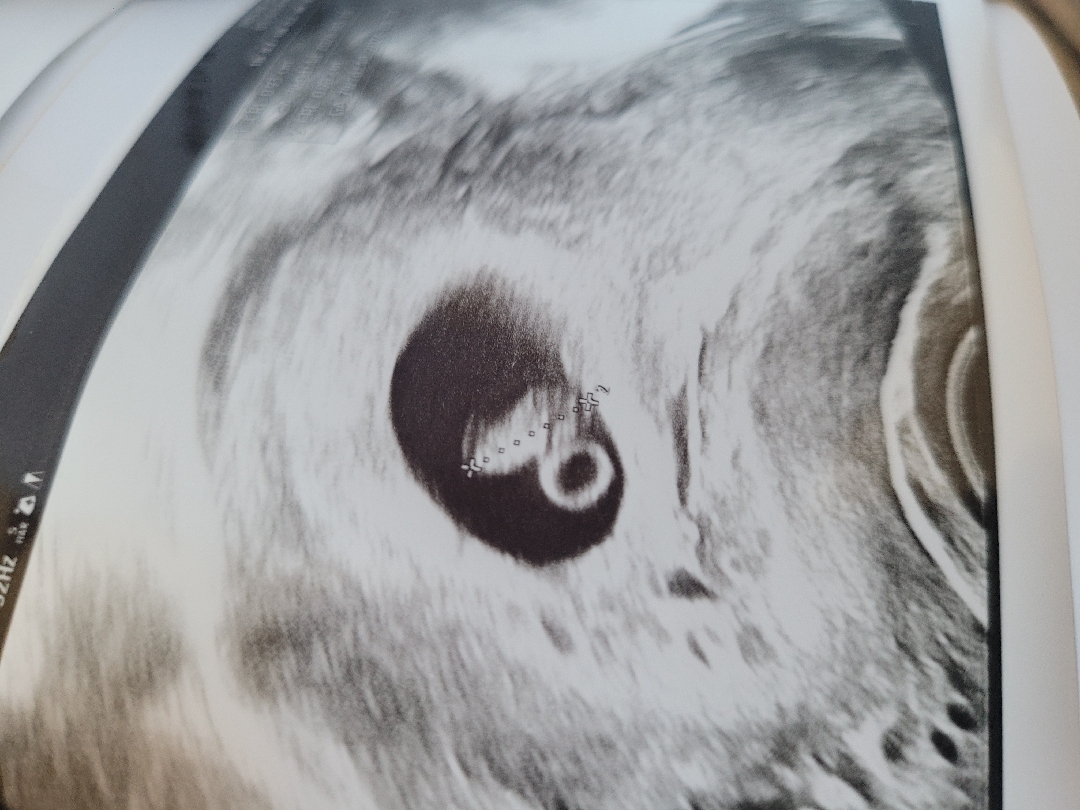

초음파보고왔어요~

임신7주차이고 심장소리도듣고 애기는 잘자라고 있다고하네요^^